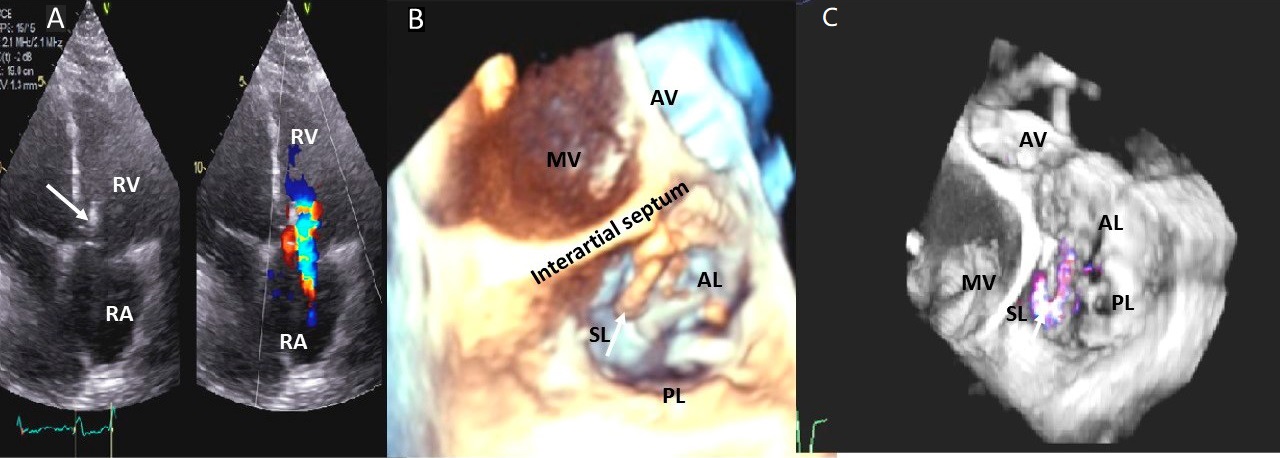

Fig. 9.Aortic valve regurgitation induced by dilated annulus. (A)

Transthoracic echocardiogram parasternal long axis view showing

markedly dilated aortic sinuses (red arrow). (B) Imaging at a higher parasternal window shows aneurysmal aortic sinuses (red arrow)

and normal ascending aorta above sinotubular junction.

(C) Three chamber view with continuous-wave (CW) Doppler showing dense AI Doppler

envelope with a steep deceleration slope (red arrows) suggesting severe AI. (D) CW Doppler recording at the proximal descending thoracic aorta

demonstrating pandiastolic flow reversal (red arrows), another feature of severe AI.

(E) Color Doppler parasternal long axis view showing AI color

jet occupying two third of the LV outflow tract with a wide vena contracta at origin from the aortic valve leaflets (

Common causes of leaflet malfunction causing AR include degenerative leaflet calcifications, and infective endocarditis (Fig. 10), bicuspid aortic valve perforation and rheumatic fever. The causes of AR include Marfan’s syndrome, annulo-aortic ectasia (idiopathic root dilatation) (Fig. 9), aortic dissection, connective tissue disease, and syphilis. The Carpentier classification is also widely used to describe the mechanism of AR [63].